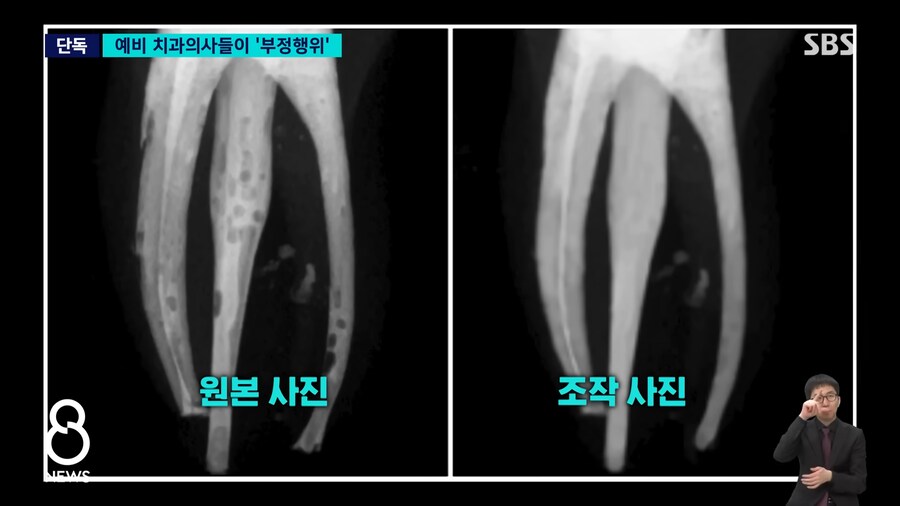

교수에게 제출한 사진

포토샵등으로 검은 부분 메꿔서 제출...

의사면허 시험 앞둔 본과 4학년 59명이 수강했고

이중에 34명이 과제 베끼고 조작..